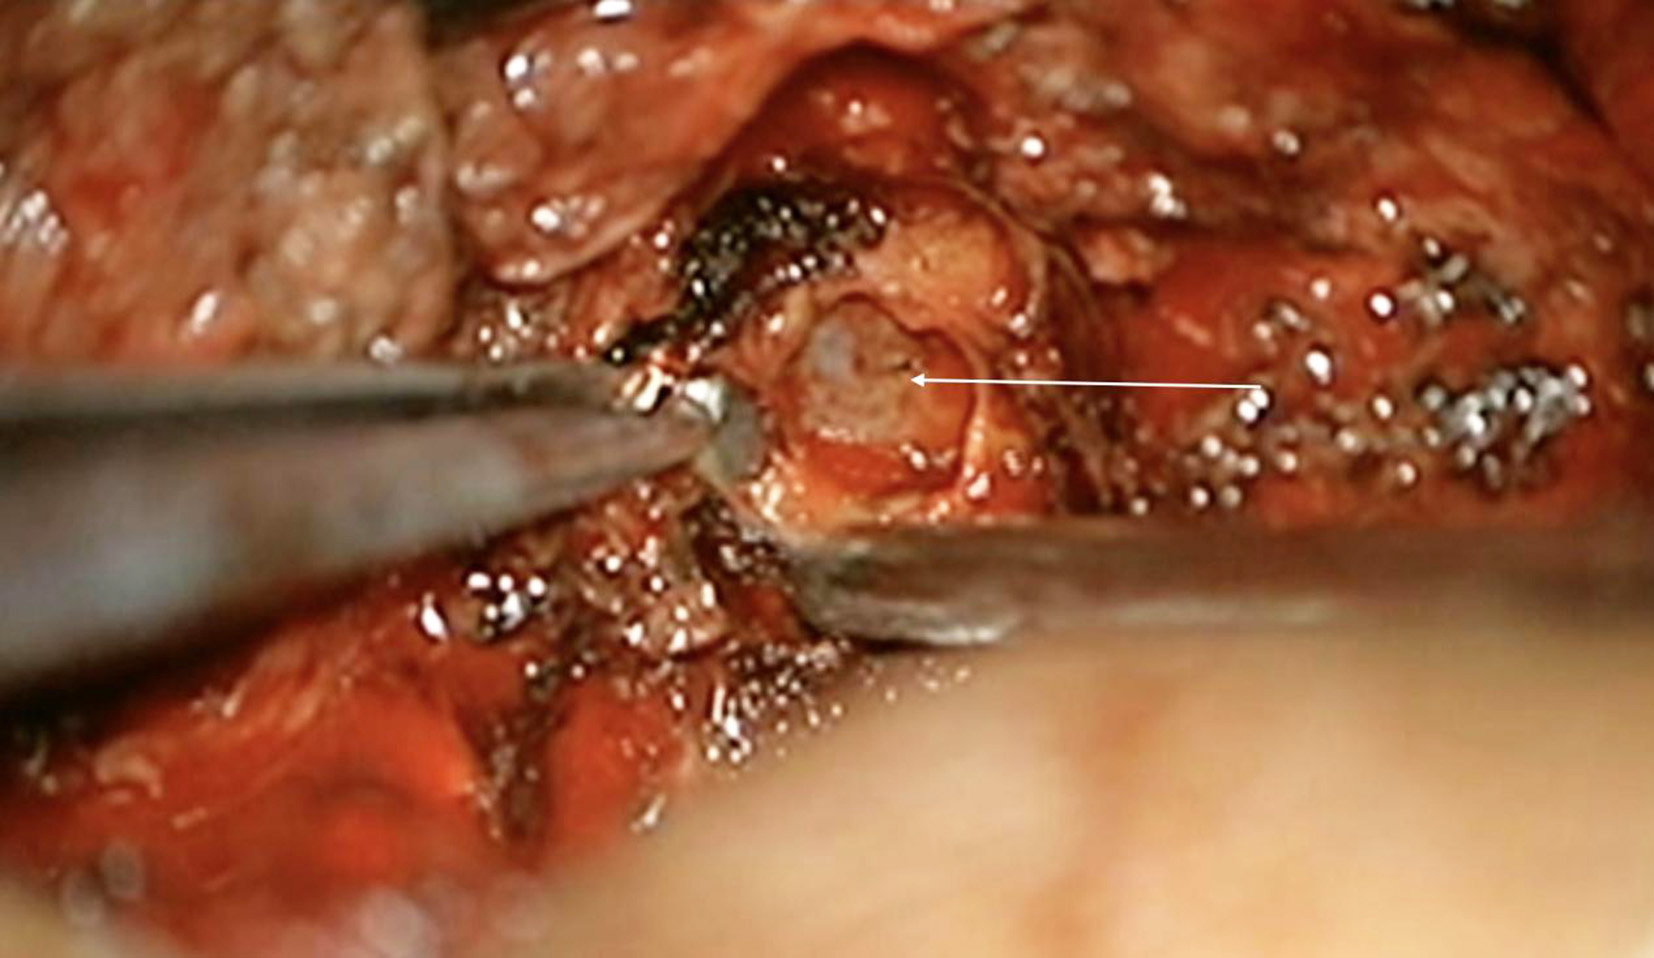

The patient underwent left transparsinterarticularis approach under general anesthesia and tumour was identified. Grossly, the tumour was blackish in colour, highly vascular and adherent to adjacent structures and the dura arising from the exiting dorsal nerve root (Fig.3). The tumour was meticulously dissected from the dura and surrounding tissues; the involved dorsal nerve root was sacrificed (Fig. 4). The lateral portion of the tumour was found adherent to pleura and was excised (Fig. 5). The total duration of surgery was 120 minutes, with an estimated blood loss of approximately 150 ml.

Fig. 3. Melanotic lesion observed lateral to thecal sac extending transforaminally (white arrow)

Fig.5. Careful dissection of the lateral portion of the tumour from the parietal pleura (white arrow)